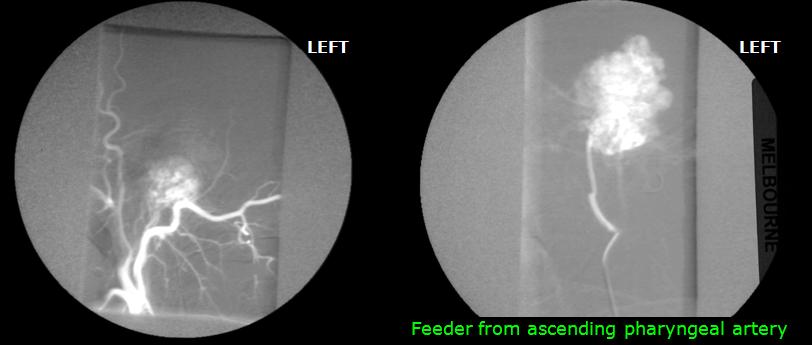

The CT scan shows the bone destructive lesion in the left petrous temporal bone in a patient with headache and ringing in the left ear.

A highly vascular lesion consistent with a glomus tumour was seen as the cause of the bony defect on the MR scan.

Angiography demonstrates a very vascular mass fed by the ascending pharyngeal artery as they often are.

During the embolisation procedure it was noted that the patient did not converse with the radiologist and a cerebrovascular accident was suspected, here confirmed by a filling defect in the left middle cerebral artery.

Immediate thrombolysis removed the blood clot and restored patient consciousness.